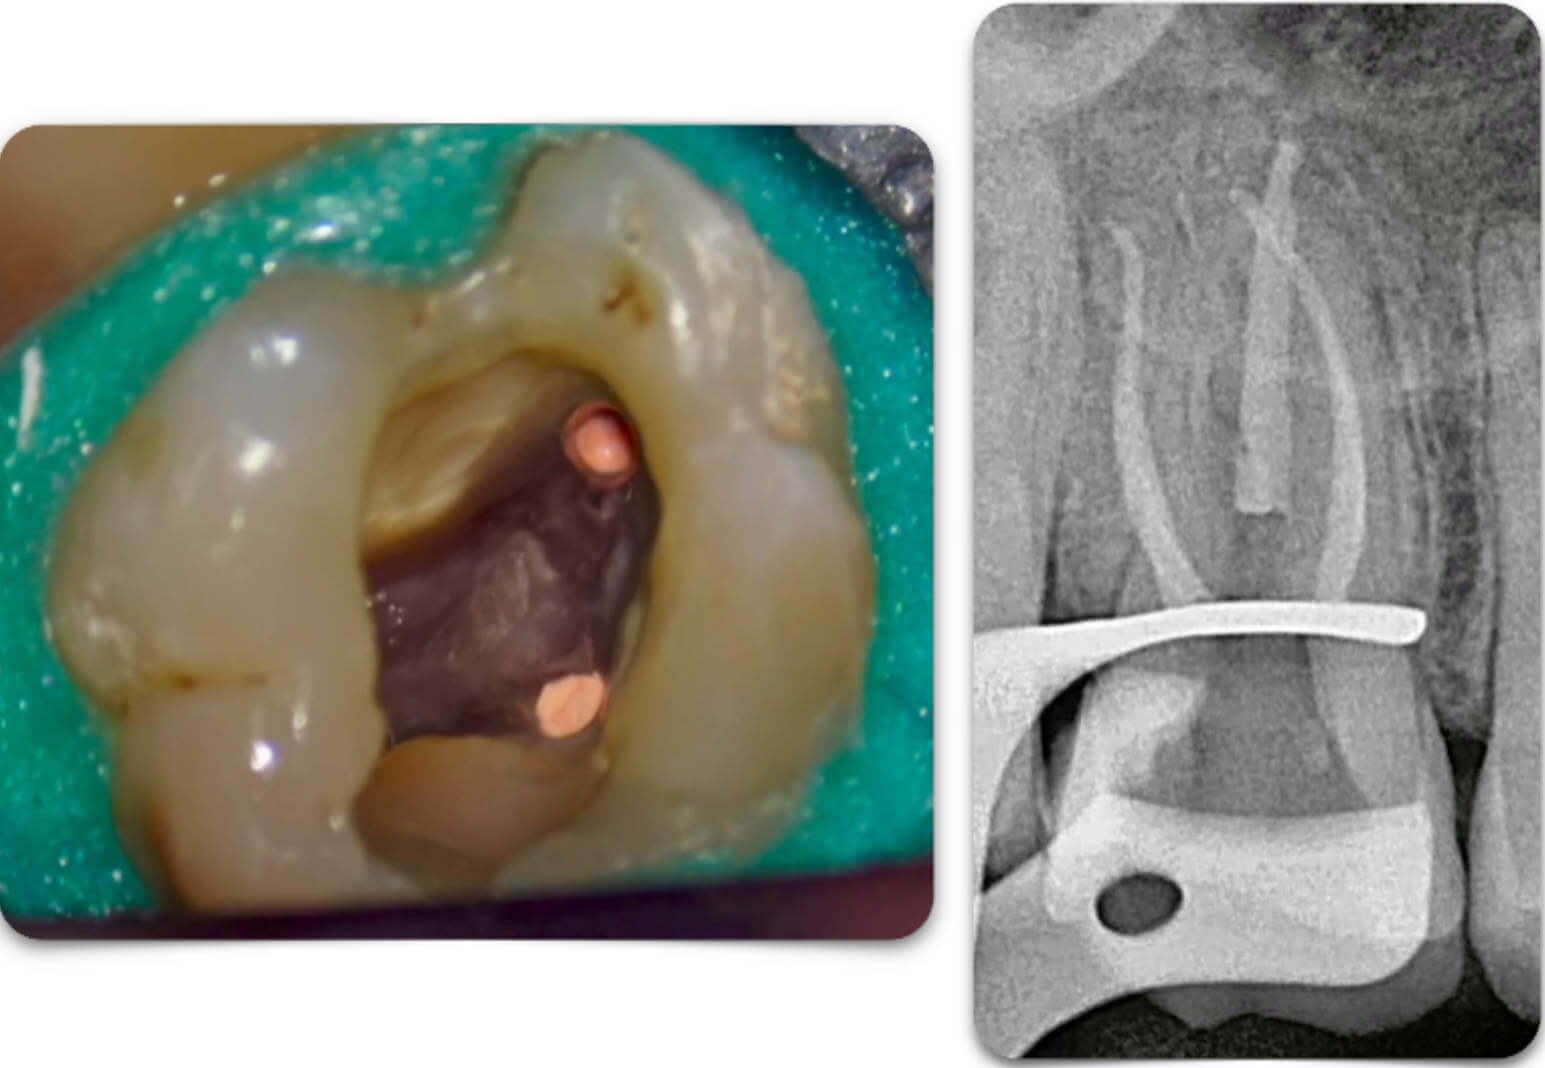

Fig. 3

Fig. 3

POST - Op Radiograph

the ledge was bypassed successfully as well you can notice how conservative the retreatment was.